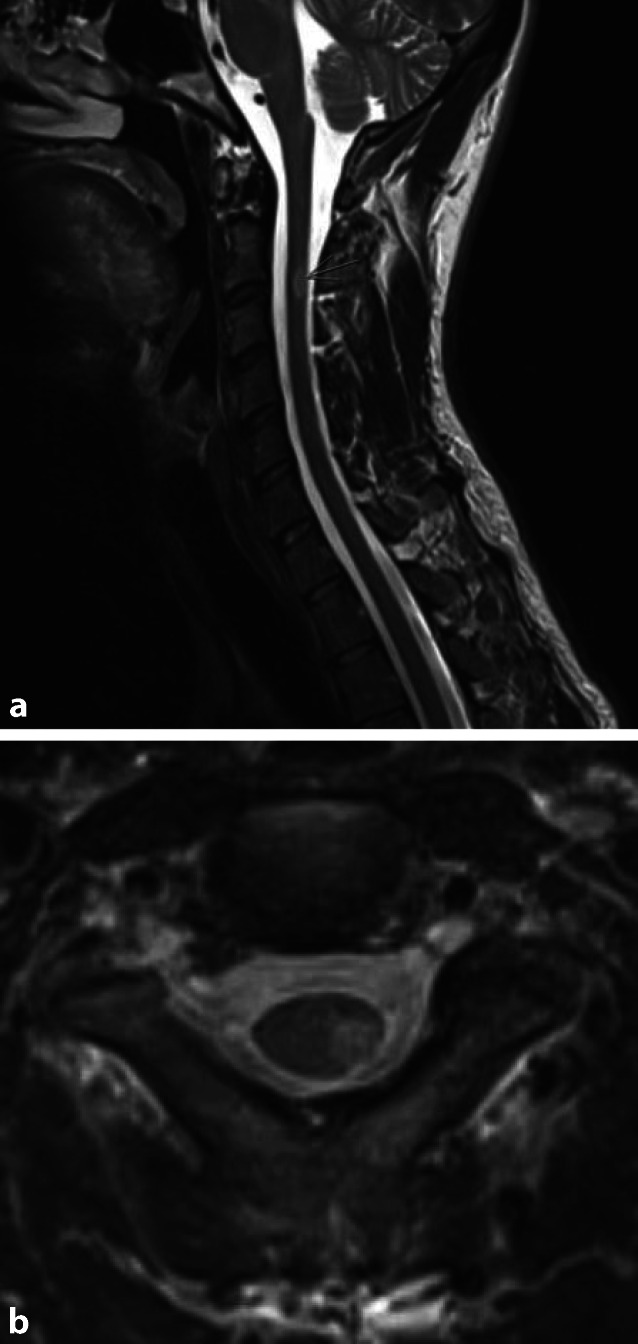

Multiple Sklerose

Die MS ist in unseren Breitengraden die häufigste demyelinisierende Erkrankung. Bei etwa 90 % der Patienten ist das Myelon mitbetroffen, und bei etwa 20 % alleiniger Manifestationsort [8]. Die Läsionen bevorzugen das Zervikalmark und sind unter 2 Segmente lang. Meist sind sie peripher dorsolateral gelegen mit einer ovoiden Form (Abb. 1a, b). Die graue Substanz ist deutlicher betroffen als im Gehirn. Typischerweise sind weniger als 50 % des Myelonquerschnitts entzündlich verändert, und akute Läsionen sind im allgemeinen kontrastmittelaffin, wobei es gelegentlich zu einer randständigen Kontrastmittelaufnahme und einer Restriktion in der diffusionsgewichteten Bildgebung (DWI) kommen kann. Dabei korreliert nicht die Anzahl der Läsionen, sondern das Ausmaß der spinalen Atrophie mit der körperlichen Behinderung. Bei der progressiven MS kann diese sogar als prädiktiver Marker für den Verlauf der Erkrankung dienen.